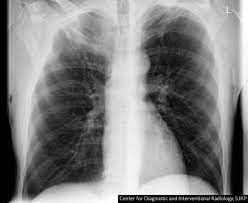

Early Signs Of Lung Cancer On Ct Scan - Google Says Its Ai Could Detect Early Signs Of Cancer Cnet : Lung nodules are tiny collections of tissue that appear in the lungs.. The larger nodules are more likely to be cancerous. How a ct scan works However, it can occur in other heart and lung diseases. Because many cases of lung cancer are not diagnosed early, as a first step in early detection, it is important to familiarize yourself with some of the early symptoms of the disease, which can include: Ct (or cat) stands for computed (axial) tomography.

One of the first signs of lung cancer that usually people tend to dismiss is a new cough that tends to persist. The ct scan might show signs of cancer, but that cancer might not be active for example, it could be scar tissue left over from cancer killed off by your treatment While it might seem obvious to assume that finding small tumors reduces one's likelihood of dying from lung cancer, this is incorrect. These small differences in lung nodules show on ct scans and can indicate if a nodule is cancerous or not. Changes in breathing can occur if lung cancer blocks or narrows an airway, or if fluid from a lung tumor.

What Are The Chances A Lung Nodule Or Spot Is Cancer Health Essentials From Cleveland Clinic from 2rdnmg1qbg403gumla1v9i2h-wpengine.netdna-ssl.com Doctors would often require you to take ct scans to be able to diagnose your condition properly. While it might seem obvious to assume that finding small tumors reduces one's likelihood of dying from lung cancer, this is incorrect. It takes pictures from different angles. Ct (or cat) stands for computed (axial) tomography. Screening external icon means testing for a disease when there are no symptoms or history of that disease. Using advanced medical imaging equipment known as a. In diagnosing lung cancer, but their role in checking whether treatment is working is unproven. Lung cancer screening is recommended for older adults who are longtime smokers and who don't have any signs or symptoms of lung cancer.

One of the first signs of lung cancer that usually people tend to dismiss is a new cough that tends to persist. Changes in breathing can occur if lung cancer blocks or narrows an airway, or if fluid from a lung tumor. This mass will look like a white spot on. A persistent cough not related to an illness. Ct (or cat) stands for computed (axial) tomography. As reviewed by bram van ginneken, phd, of the radboud university medical center in the netherlands, quantitative measures obtained from a chest ct scan may enable the early detection of different obstructive and interstitial lung diseases, such as chronic obstructive. Shortness of breath or becoming easily winded are also possible symptoms of lung cancer. The term tomography comes from the greek words tomos (a cut, a slice, or a section) and graphein (to write or record). The mayo clinic lists some of the common symptoms of lung cancer, which range from general hoarseness to coughing up blood. Each picture created during a ct procedure. When people experience signs and symptoms of lung cancer, the early ones may include any of the following: However, if it is an early warning sign of lung cancer, then this persistent cough will tend to linger. Without screening, 70 percent of lung cancers are found at a later stage when there is little chance for a cure.

Each picture created during a ct procedure. The main benefit of lung cancer screening is preventing death from lung cancer. Lung nodules are tiny collections of tissue that appear in the lungs. Lung cancer screening finds 80 percent of lung cancer at an early stage when it is more curable. Lung cancer can sometimes be detected in its early stages with a lung scan.

Researchers Using Artificial Intelligence To Detect Early Signs Of Lung Pancreatic Cancers Abc7 Los Angeles from cdn.abcotvs.com Patients with lung cancer may be asymptomatic in up to 50% of cases. Early detection is the key. Ct scan for lung cancer. The mayo clinic lists some of the common symptoms of lung cancer, which range from general hoarseness to coughing up blood. Changes in breathing can occur if lung cancer blocks or narrows an airway, or if fluid from a lung tumor. When people experience signs and symptoms of lung cancer, the early ones may include any of the following: It is used to look for early signs of lung cancer. Pneumonia, pleural effusion, wheeze, lymphadenopathy are not uncommon.

Patients with lung cancer may be asymptomatic in up to 50% of cases. Around 40 percent of lung nodules are cancerous (malignant). They appear due to scarring caused by a previous infection or a benign tumor. If the test finds cancer, treatment can start early. Each picture created during a ct procedure. It is sometimes called computerized tomography or computerized axial tomography (cat). Ldct scans can help find abnormal areas in the lungs that may be cancer. Find out if you are eligible for the early lung cancer detection program. The term tomography comes from the greek words tomos (a cut, a slice, or a section) and graphein (to write or record). Ct scans are inaccurate for treatment monitoring after cancer treatment, a ct scan is unable to determine whether masses leftover are cancerous: It is detectable by early symptoms such as constant coughing, chest pain, and many more. While it might seem obvious to assume that finding small tumors reduces one's likelihood of dying from lung cancer, this is incorrect. So what does a lung ct scan show?

What Are The Chances A Lung Nodule Or Spot Is Cancer Health Essentials From Cleveland Clinic from 2rdnmg1qbg403gumla1v9i2h-wpengine.netdna-ssl.com Ct scan for lung cancer. Ct scans are inaccurate for treatment monitoring after cancer treatment, a ct scan is unable to determine whether masses leftover are cancerous: It is sometimes called computerized tomography or computerized axial tomography (cat). Lung cancer screening is recommended for older adults who are longtime smokers and who don't have any signs or symptoms of lung cancer. A computer then combines these images into a detailed picture of your lungs. It takes pictures from different angles. Changes in breathing can occur if lung cancer blocks or narrows an airway, or if fluid from a lung tumor. The larger nodules are more likely to be cancerous.

Ct screening for lung cancer can reveal subtle early signs of disease in the lungs that extend beyond potential malignancy. Shortness of breath or becoming easily winded are also possible symptoms of lung cancer. Most doctors do not recommend pet/ct scans for routine follow up of patients after lung cancer treatment. The mayo clinic lists some of the common symptoms of lung cancer, which range from general hoarseness to coughing up blood. It takes pictures from different angles. a ct scan is needed if there is any concern. Lung nodules are tiny collections of tissue that appear in the lungs. Find out if you are eligible for the early lung cancer detection program. Pneumonia, pleural effusion, wheeze, lymphadenopathy are not uncommon. A persistent cough not related to an illness. Ct scans can detect cancer at a very small size. Patients with lung cancer may be asymptomatic in up to 50% of cases. It is used to look for early signs of lung cancer.